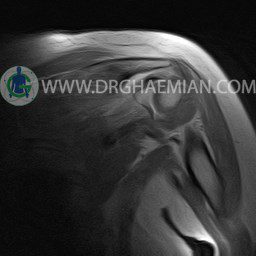

ام آر آی آتروفی عضلانی کتف بیمار

ام ار آی کتف یک روش تصویربرداری است که به وسیله آهنرباهای قدرتمند از قسمت کتف تصاویری ایجاد می کند. این نوع تصویربرداری از تشعشعات استفاده نمی کند. در این کیس آتروفی عضلانی کتف به همراه پارگی تاندون بالاخاری، بورسیت ساب دلتوئید و افیوژن مفصل دیده می شود.

– Complete tearing of supraspinatus tendon with grade 2 retraction and muscle atrophy

– AC joint hypertrophy with subacromial – subdeltoid bursitis

– Glenohumeral joint effusion

are seen.